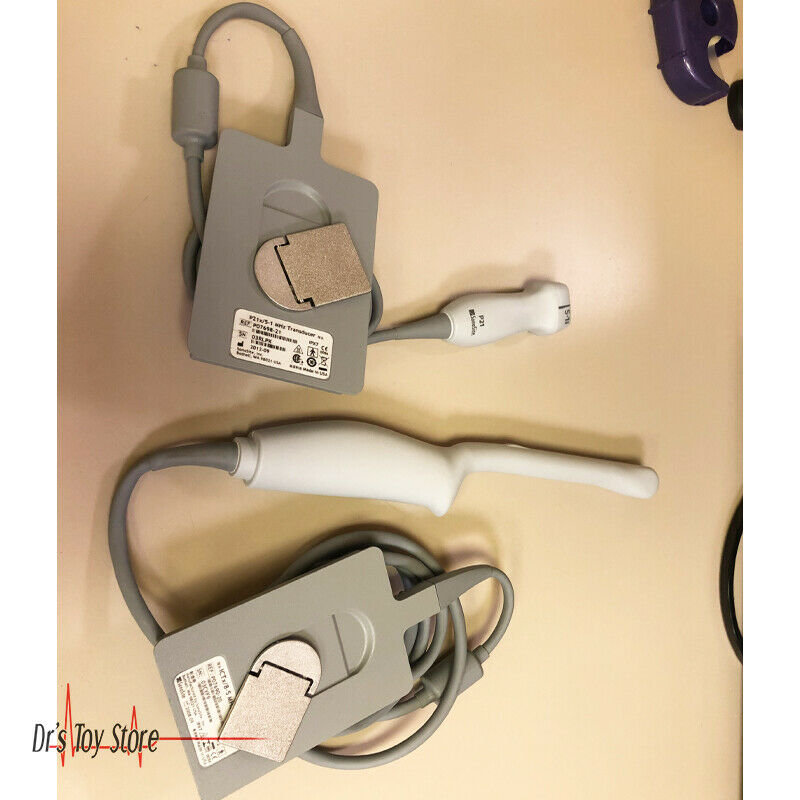

DIAGNOSTIC ULTRASOUND MACHINES FOR SALE

2017 GE IC9 -RS probe for GE Ultrasound

Sale price$ 8,395.14